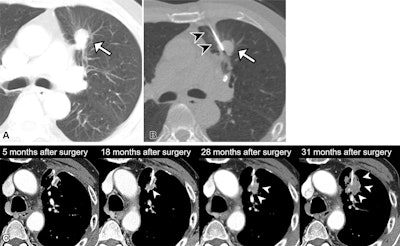

Remnant lung recurrence after percutaneous transthoracic needle biopsy (PTNB) following wedge resection. (A) Preoperative contrast-enhanced axial CT scan in a 76-year-old male patient shows a 1.8-cm solid nodule in the left upper lobe (arrow). (B) The patient underwent PTNB for nodule diagnosis. A nonenhanced axial CT scan showed that the introducer needle (arrowheads) was inserted into the inner portion of the nodule (arrow), traversing the lung parenchyma. The diagnosis on the basis of results from the PTNB was adenocarcinoma, and the patient subsequently underwent left upper lobe wedge resection 7 days after PTNB was performed. The final diagnosis was adenocarcinoma of the solid-predominant type, pT1bN0. (C) At postoperative follow-up, a nodular opacity emerged adjacent to the surgical site (arrowheads) and increased in size at subsequent imaging. This soft-tissue lesion was confirmed at PTNB as metastatic adenocarcinoma, and the patient underwent salvage radiation to treat the remnant lung recurrence.RSNA